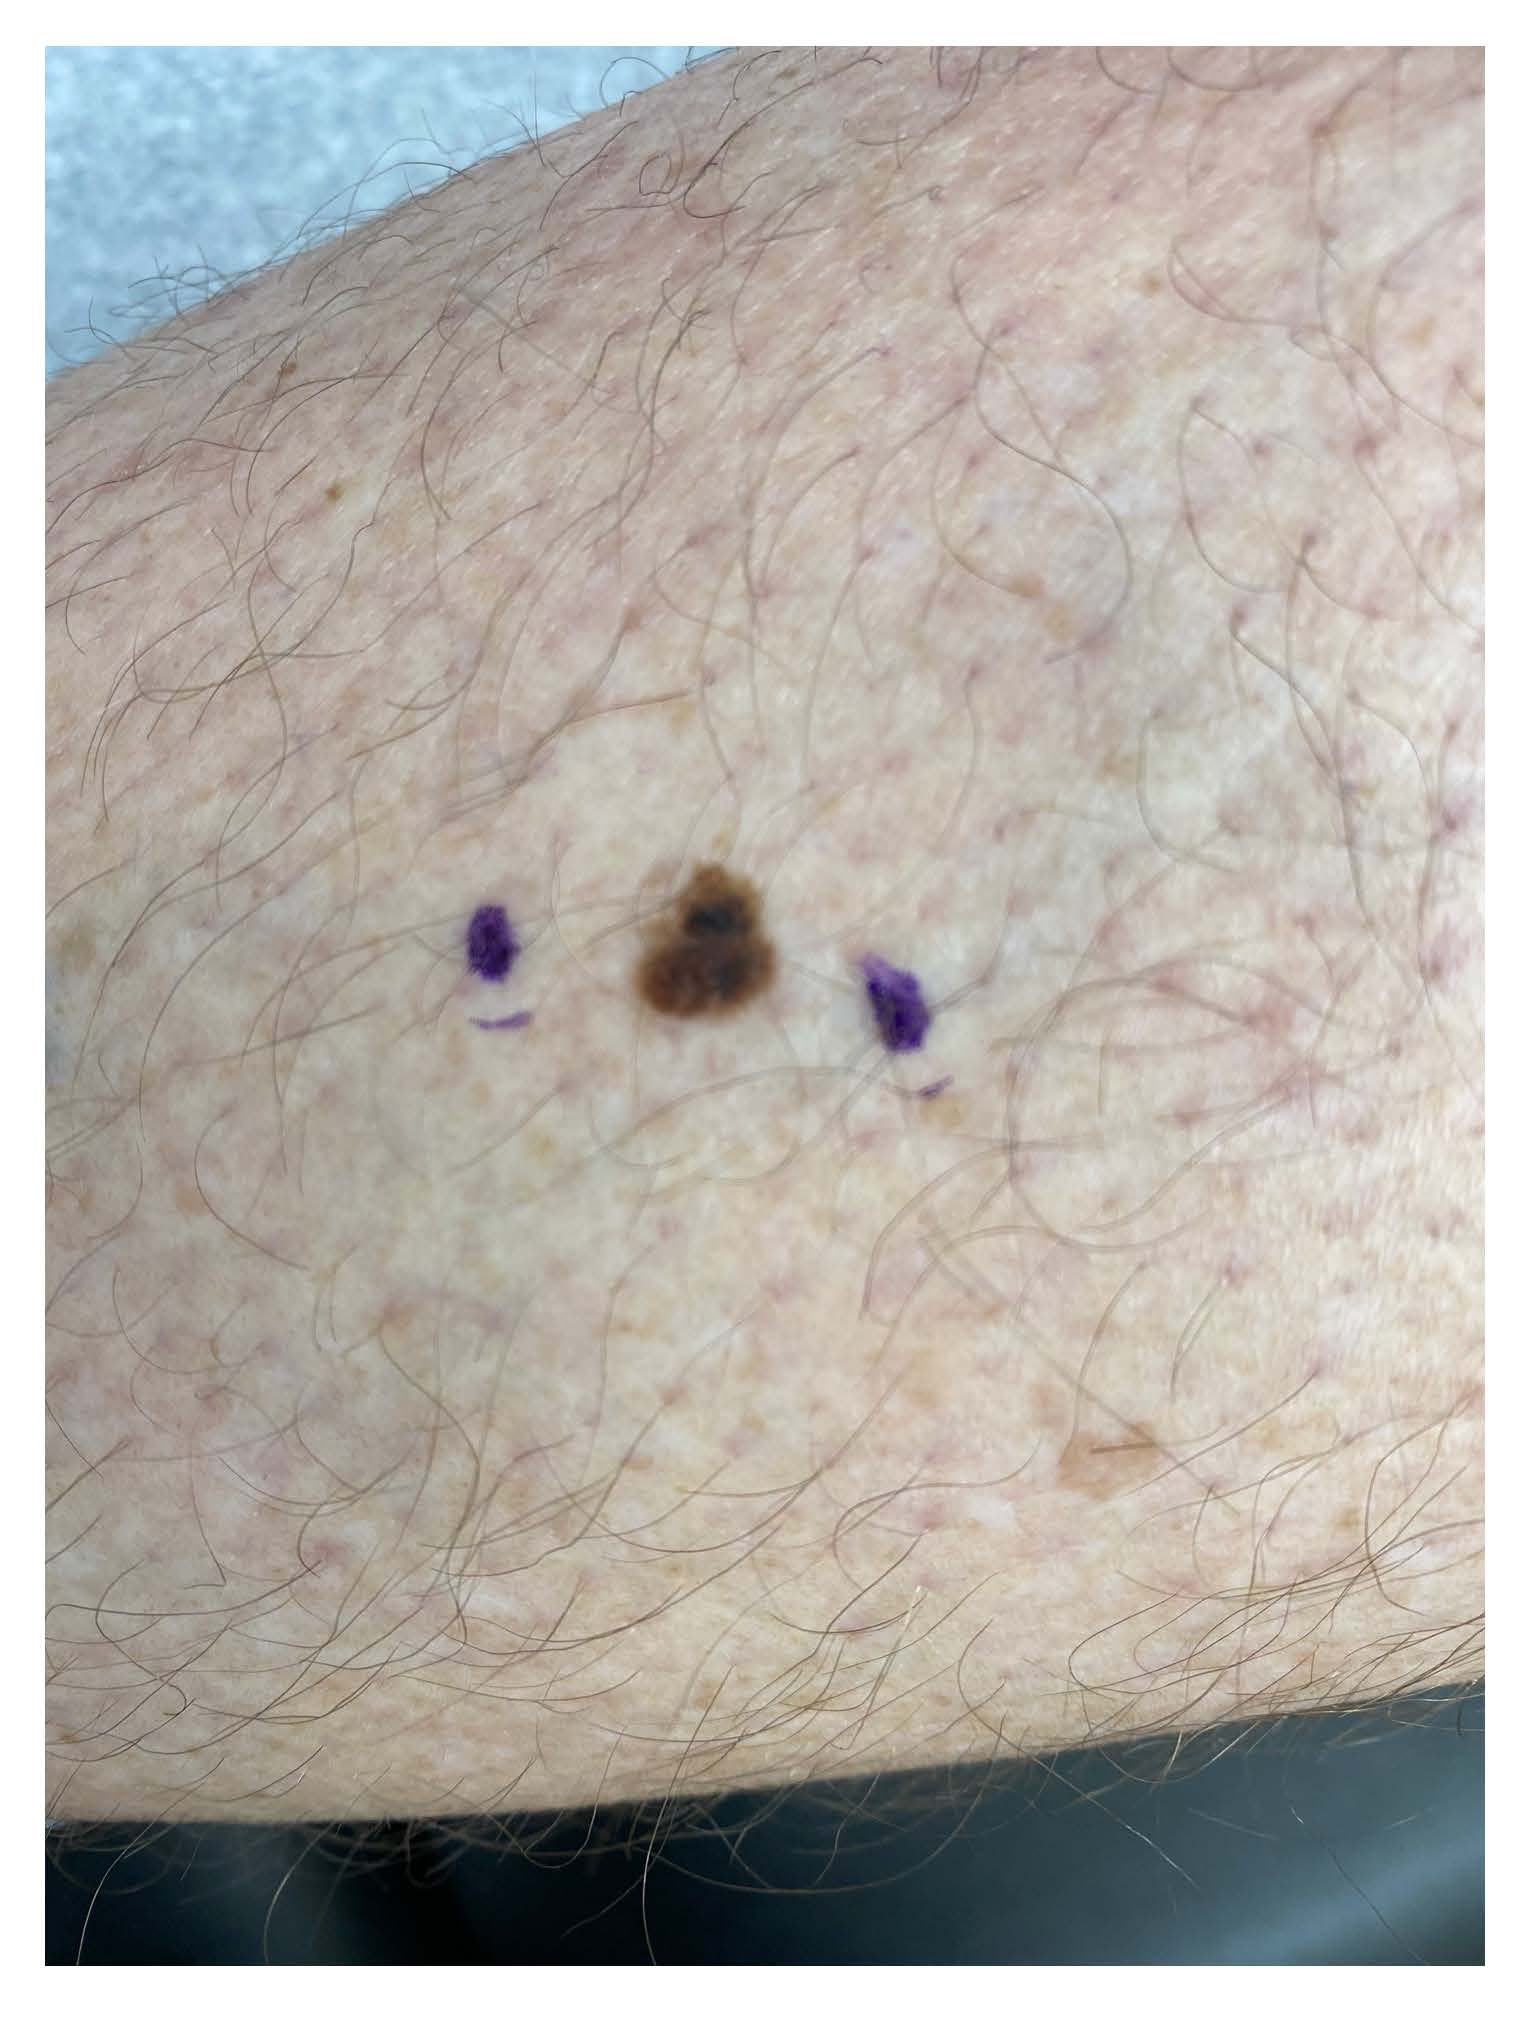

Basal cell carcinoma on the leg. Photo: International Skin Imaging Collaboration at isic-archive.com